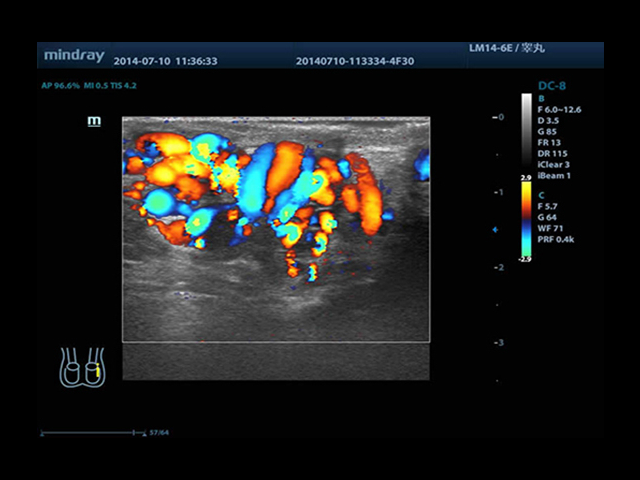

Mindray DC-8 Exp оснащен новым поколением датчиков с увеличенным количеством элементов и инновационной технологией "3T". Это позволяет достичь высокой детализации и качества изображения. Благодаря новейшей технологии iFlow, можно визуализировать даже самые мелкие сосуды и кровеносные пути.

• HR-flow™ - режим отображения кровотока с высоким временным и пространственным разрешением для точной и однородной визуализации сосудов, в том числе самых мелких